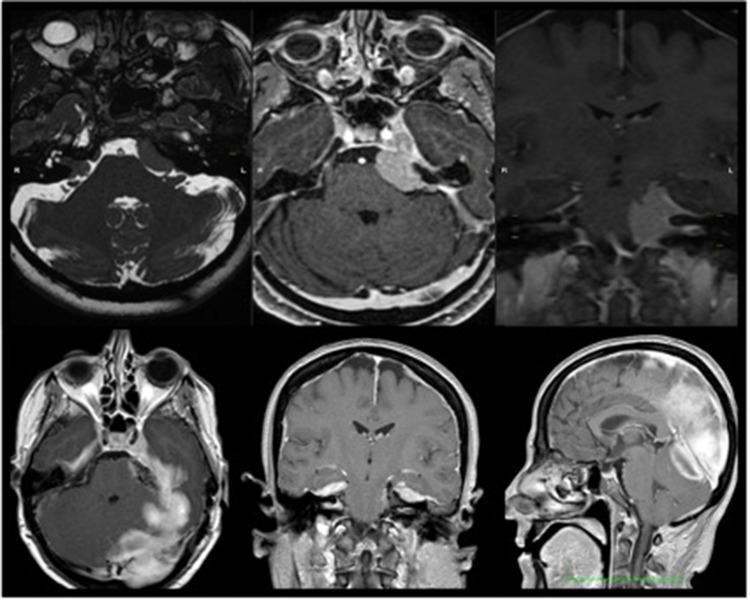

We performed a retrospective nonrandomized study to analyze the results of a microsurgery of intracranial meningiomas using 2-μm thulium flexible handheld laser fiber (Revolix jr).

From February 2014 to December 2021, 75 nonconsecutive patients suffering from intracranial meningiomas, admitted in our department, have been operated on with microsurgical technique assisted by 2-μm thulium flexible handheld laser. We have reviewed demographic and clinical data to evaluate safety and efficacy of the technique.

There were no complications related to the use of the 2-μm thulium laser. We operated on a high percentage of cranial base and tentorial and posterior fossa meningioma in our series. The neurological outcome and degree of resection did not differ from previous series. The neurosurgical team found the laser easy to use and practical for avoiding bleeding and traction.

The use of 2-μm thulium fiber handheld flexible laser in microsurgery of intracranial meningiomas seems to be safe and to facilitate tumor resection, especially in "difficult" conditions (e.g., deep seated, highly vascularized, and hard tumors). Even if in this limited retrospective trial the good functional outcome following conventional microsurgery had not further improved, nor the surgical time was reduced by laser, focusing its use on "difficult" (large and vascularized) cases may lead to different results in the future.